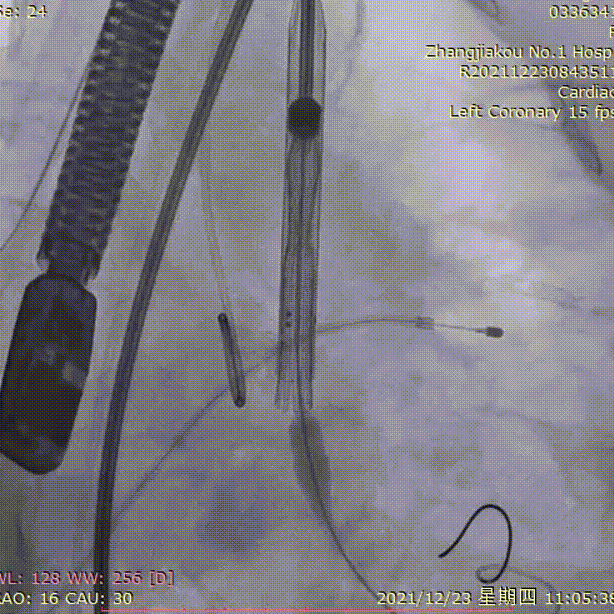

手术过程

根部造影

25mm球囊预扩

输送器过弓

初始定位